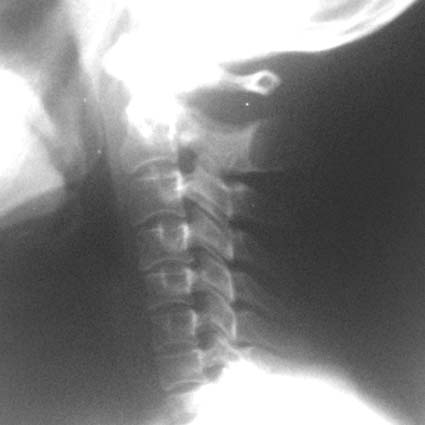

女,45岁,近来感颈部疼痛,头晕,夜不能寐,按之枢椎棘突,感有硬结感,疼痛,骨科怀疑骨囊肿,拟手术,请大家帮忙看一下,是否是正常的?

颈椎骨质增生;颈4/5、5/6椎间盘变性,未除突出,建议mr颈椎检查。

楼主所指的枢椎棘突密度减低区属正常表现,你可能多拿几个颈椎侧位片看看。

下面是我刚从网上下载的几张颈椎图片。

生理曲度变直